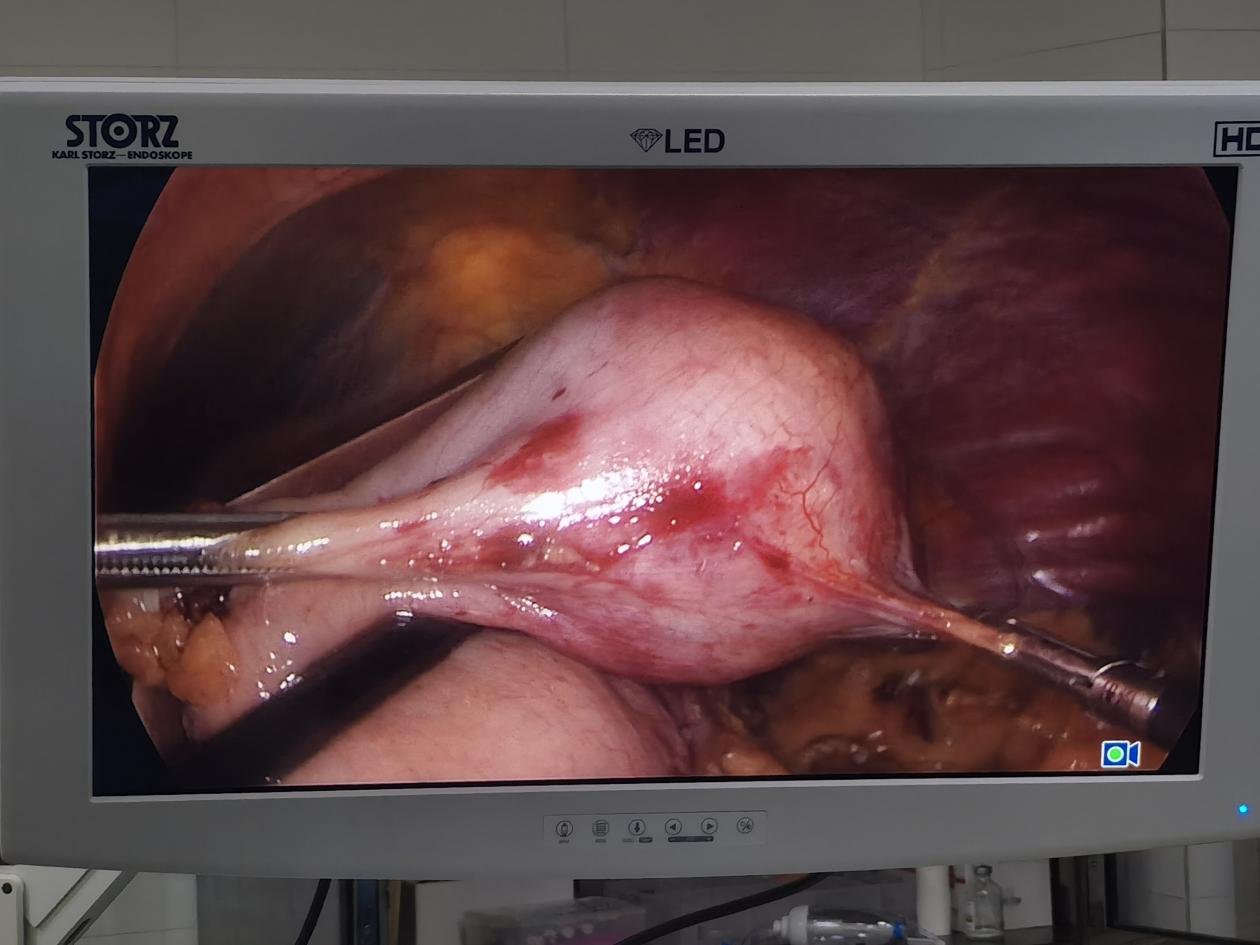

术中图片